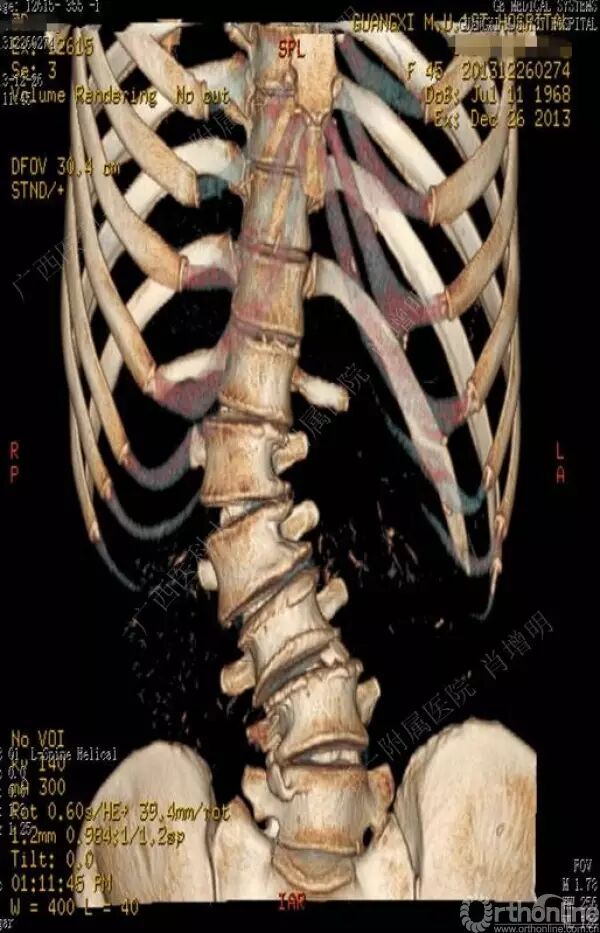

退变性脊柱侧凸是由于椎间盘退变后继发小关节退变,椎管和神经根管容积变化以及脊柱失稳,畸形等病理改变,以疼痛和神经压迫症状为主要表现的常见疾病。

退变性脊柱侧凸多发于50岁以上的中老年群体,是现代常见的老年疾病。多年来,针对该病的临床研究一直没有停步,广西医科大学第一附属医院肖增明教授细致地介绍了该病的诊疗进展。